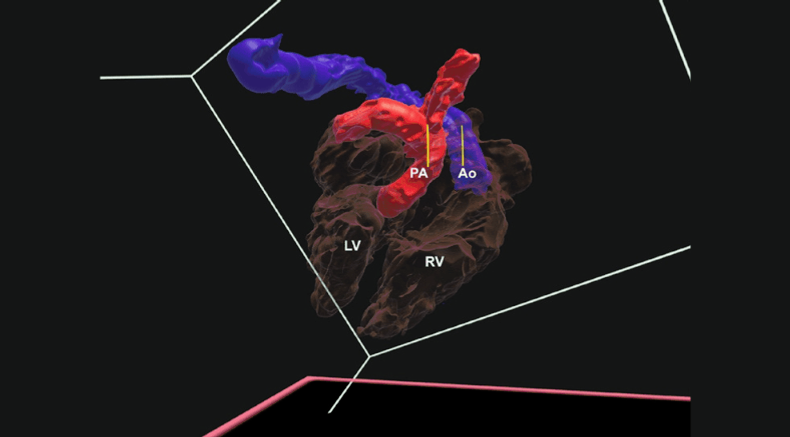

Three-dimensional virtual model of fetal heart showing transposition of the great arteries

Leite, M.d.F.P., Bravo-Valenzuela, N.J., Araujo Júnior, E., Ribeiro, G., Arcoverde, V. and Werner, H. (2025), Transposition of the great arteries: three-dimensional virtual navigation inside the fetal heart. Ultrasound Obstet Gynecol, 66: 669-671. https://doi.org/10.1002/uog.70032

Virtual rendering of fetal heart with transposition of the great arteries with cardiac structures segmented by colour for the purpose of virtual navigation

Leite, M.d.F.P., Bravo-Valenzuela, N.J., Araujo Júnior, E., Ribeiro, G., Arcoverde, V. and Werner, H. (2025), Transposition of the great arteries: three-dimensional virtual navigation inside the fetal heart. Ultrasound Obstet Gynecol, 66: 669-671.